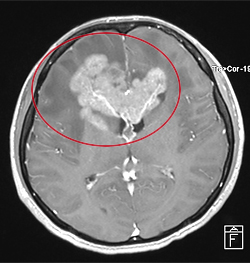

悪性腫瘍の手術前

手術後

放射線・化学療法後